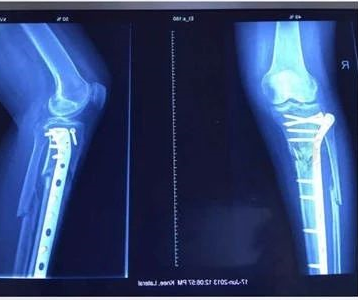

根据临床及叉线的证据,骨折治疗后超过一般愈合时间且再度延长治疗时间仍达不到骨性愈合,显示骨修复已停止,可诊断为骨折不愈合,骨折不愈合的最终表现为假关节形成。ESWT治疗骨折不愈合的原理与治疗骨折延迟愈合类似,并且具有良好效果。